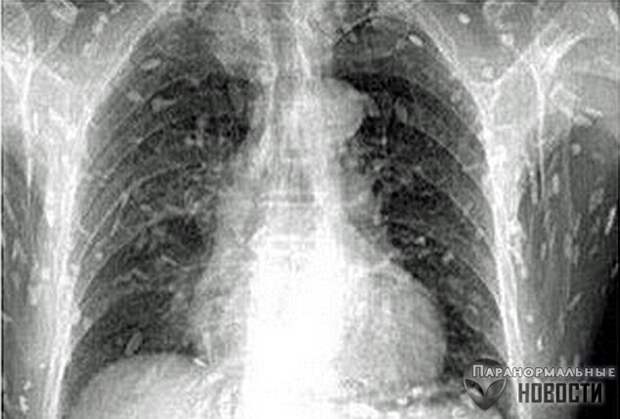

Житель провинции Гуандун обратился в больницу с жалобами на боли в животе - и рентген показал, что все его органы буквально оккупированы червями-солитерами.

Врачи считают,что причиной этого стало увлечение мужчины суши, он постоянно ел их с сырой рыбой. Червей в его организме было так много, что первым его порывом, когда он увидел на рентгене копошащуюся армию паразитов внутри себя, было сигануть из окна. Его успели остановить.